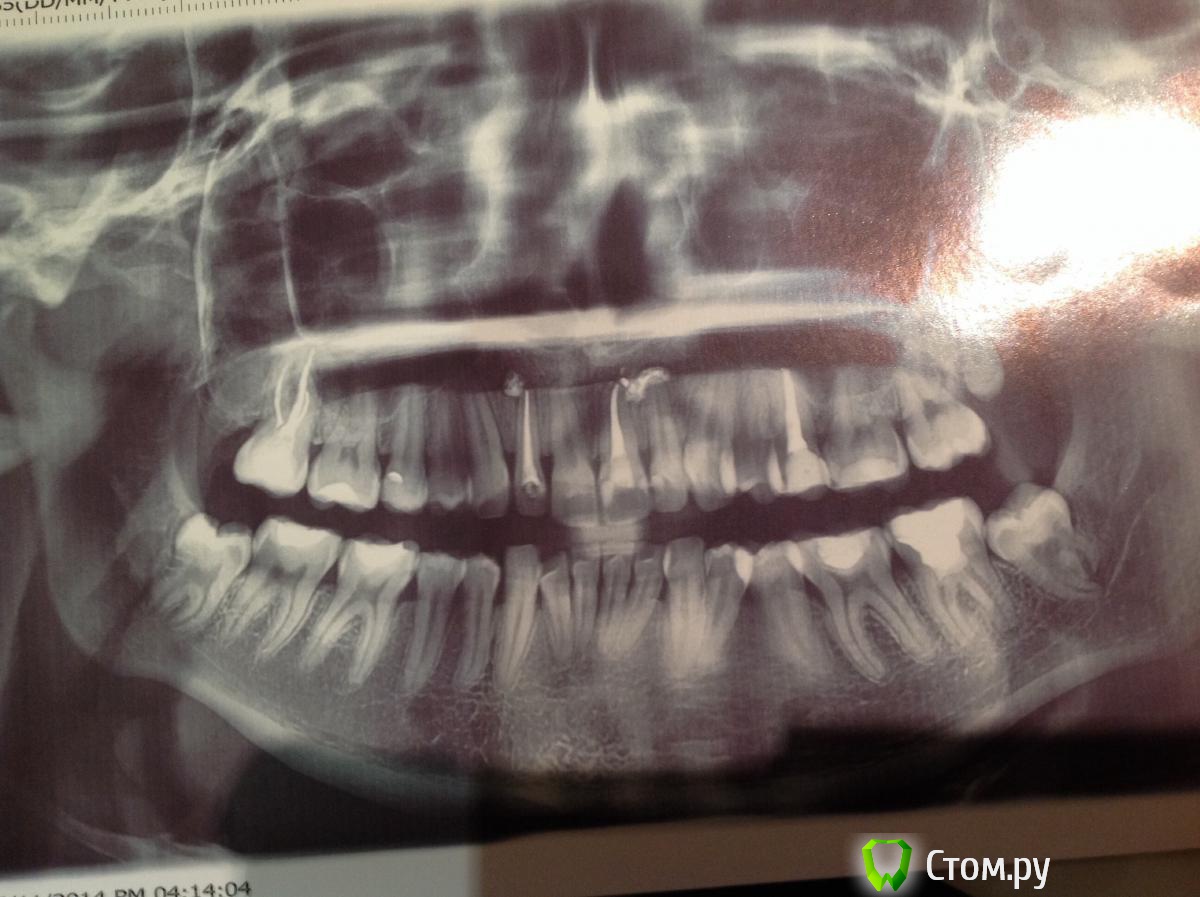

Алина52 Опубликовано 26 ноября, 2014 Поделиться Опубликовано 26 ноября, 2014 Прошу проконсультироваться. Ставили брекеты дочерей на верхнюю и нижнюю челюсти. После снятия, врач сказал одевать скобки на ночь. Что и делали примерно 1 год. Однако спустя какое то время оказалось, что идет процесс рецессию десен. Проходили физиолечение , сейчас врачи разводят руками, говорят вплоть до хирургического вмешательства. Очень не хочется ошибиться с лечение, как при брекета, когда врач не поставил ретейнеры. Понимаю, что сложно судить со слов. Возможно снимок поможет. Заранее спасибо за помощь. Ссылка на комментарий